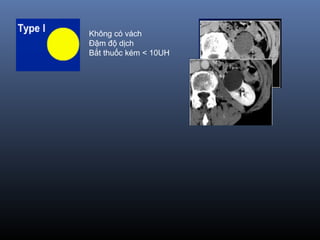

Phân lo i BosniakạType I Nang đ n thu nơ ầ :

Đ m đ d ch(-10-20 UH), đ ng d ng,gh rõ, không th y v ,không b tậ ộ ị ồ ạ ấ ỏ ắ

thu c c n quangố ả

=> Lành tính, không c n theo dõiầ

Không có vách

Bắt thuốc kém < 10UH